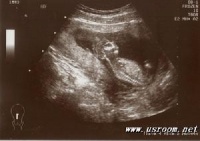

1.超声检查:羊水平段>7cm示合并羊水过多,测不出胎儿双顶径。B型超声波声像图不见胎头之光环。